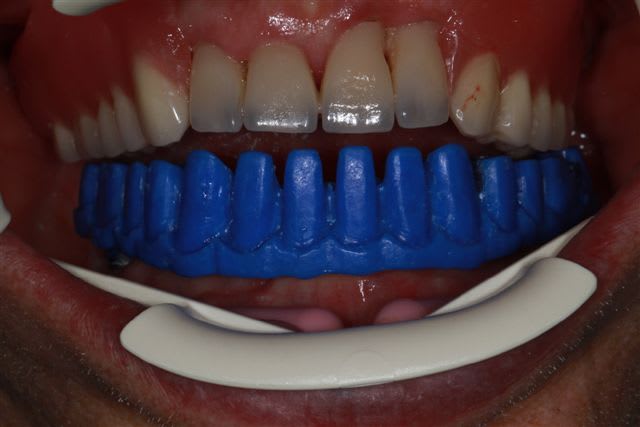

et dans le même esprit, il n'y a pas que la cadcam, ce matin essayage de la maquette (résine calcinable+cire)pour controler l'ajustage et surtout valider la préforme pour l'occlusion,et la position des incisives.

Moralité nous allons repositionner la fausse gencive et les incisives...(ce sera une barre avec emax press dessus)